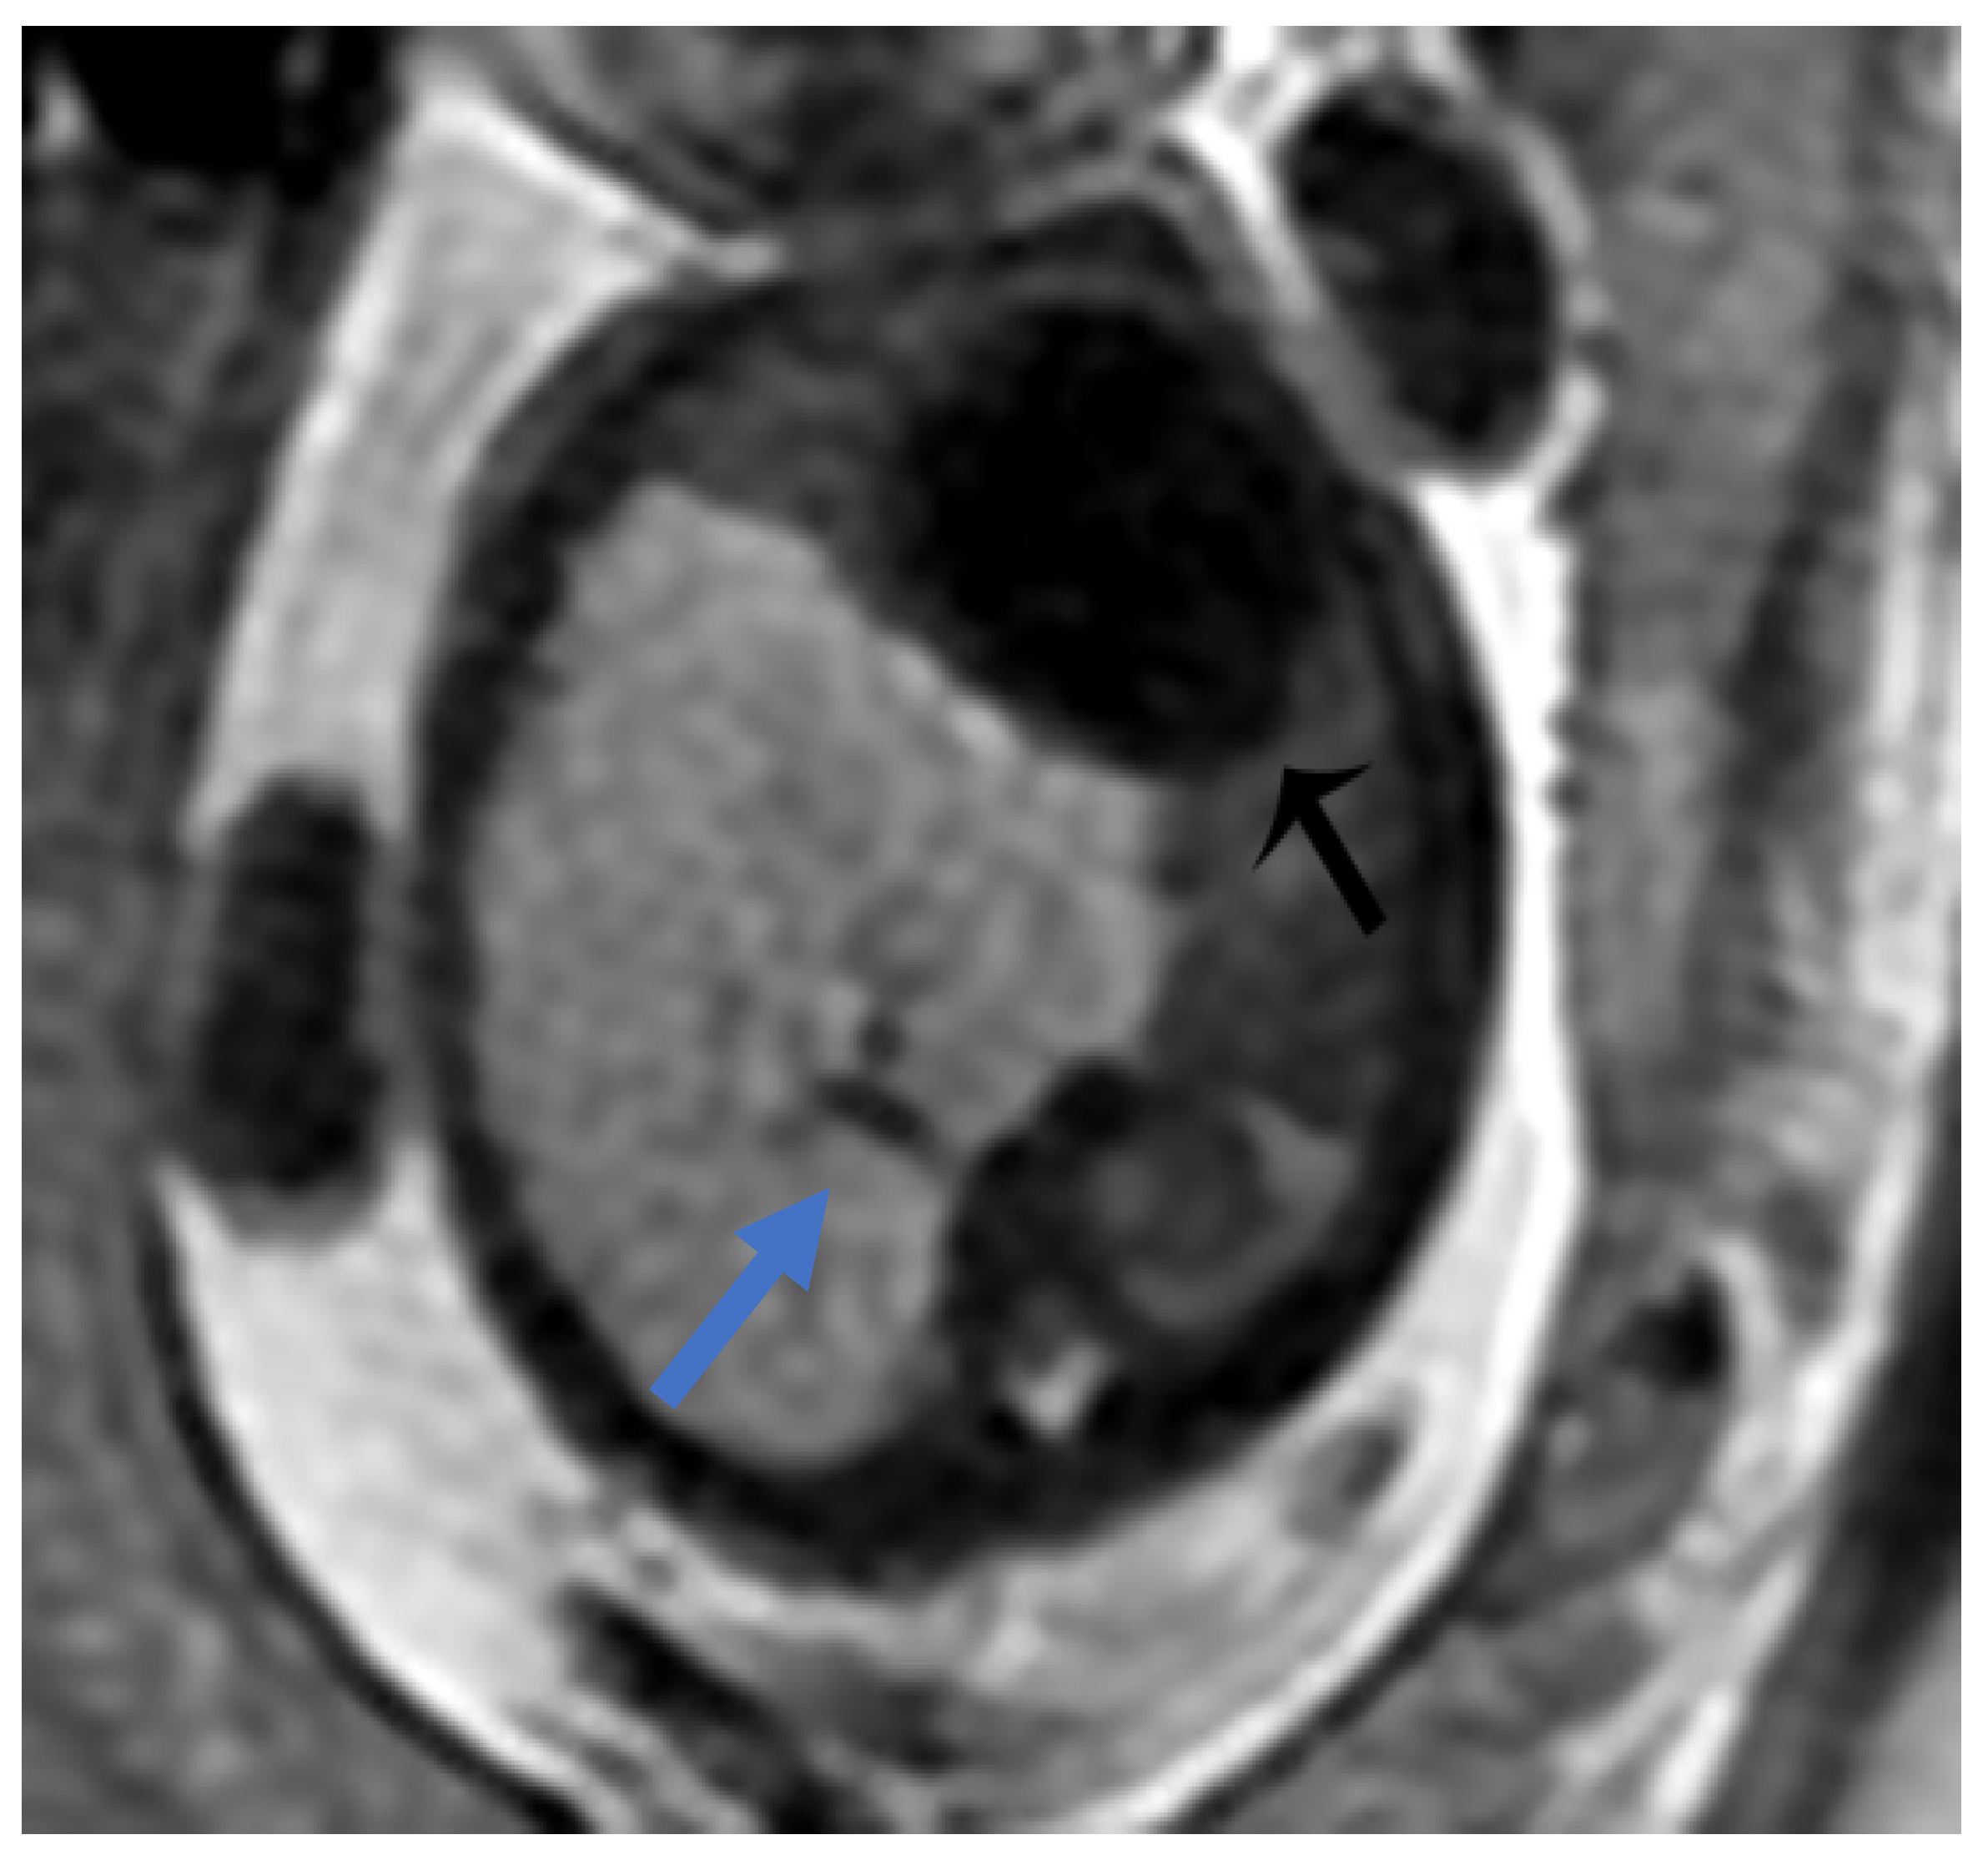

In prenatal diagnosis, MRI is valuable for better delineating and locating the mass. It also helps in assessing the contralateral lung. Key diagnostic signs on MRI include higher signal intensity than normal lung tissue, lower signal intensity than amniotic fluid, and the visible supply artery arising from the aorta (Figure 7) [8,11].

Figure 7. BPS at 27 weeks gestation. The coronal image shows a mass with higher signal intensity than the normal lung but lower signal intensity than amniotic fluid. The consolidation shifts the heart to the right (black arrow). There is a feeding artery from the aorta to suggest the diagnosis of sequestration (blue arrow).